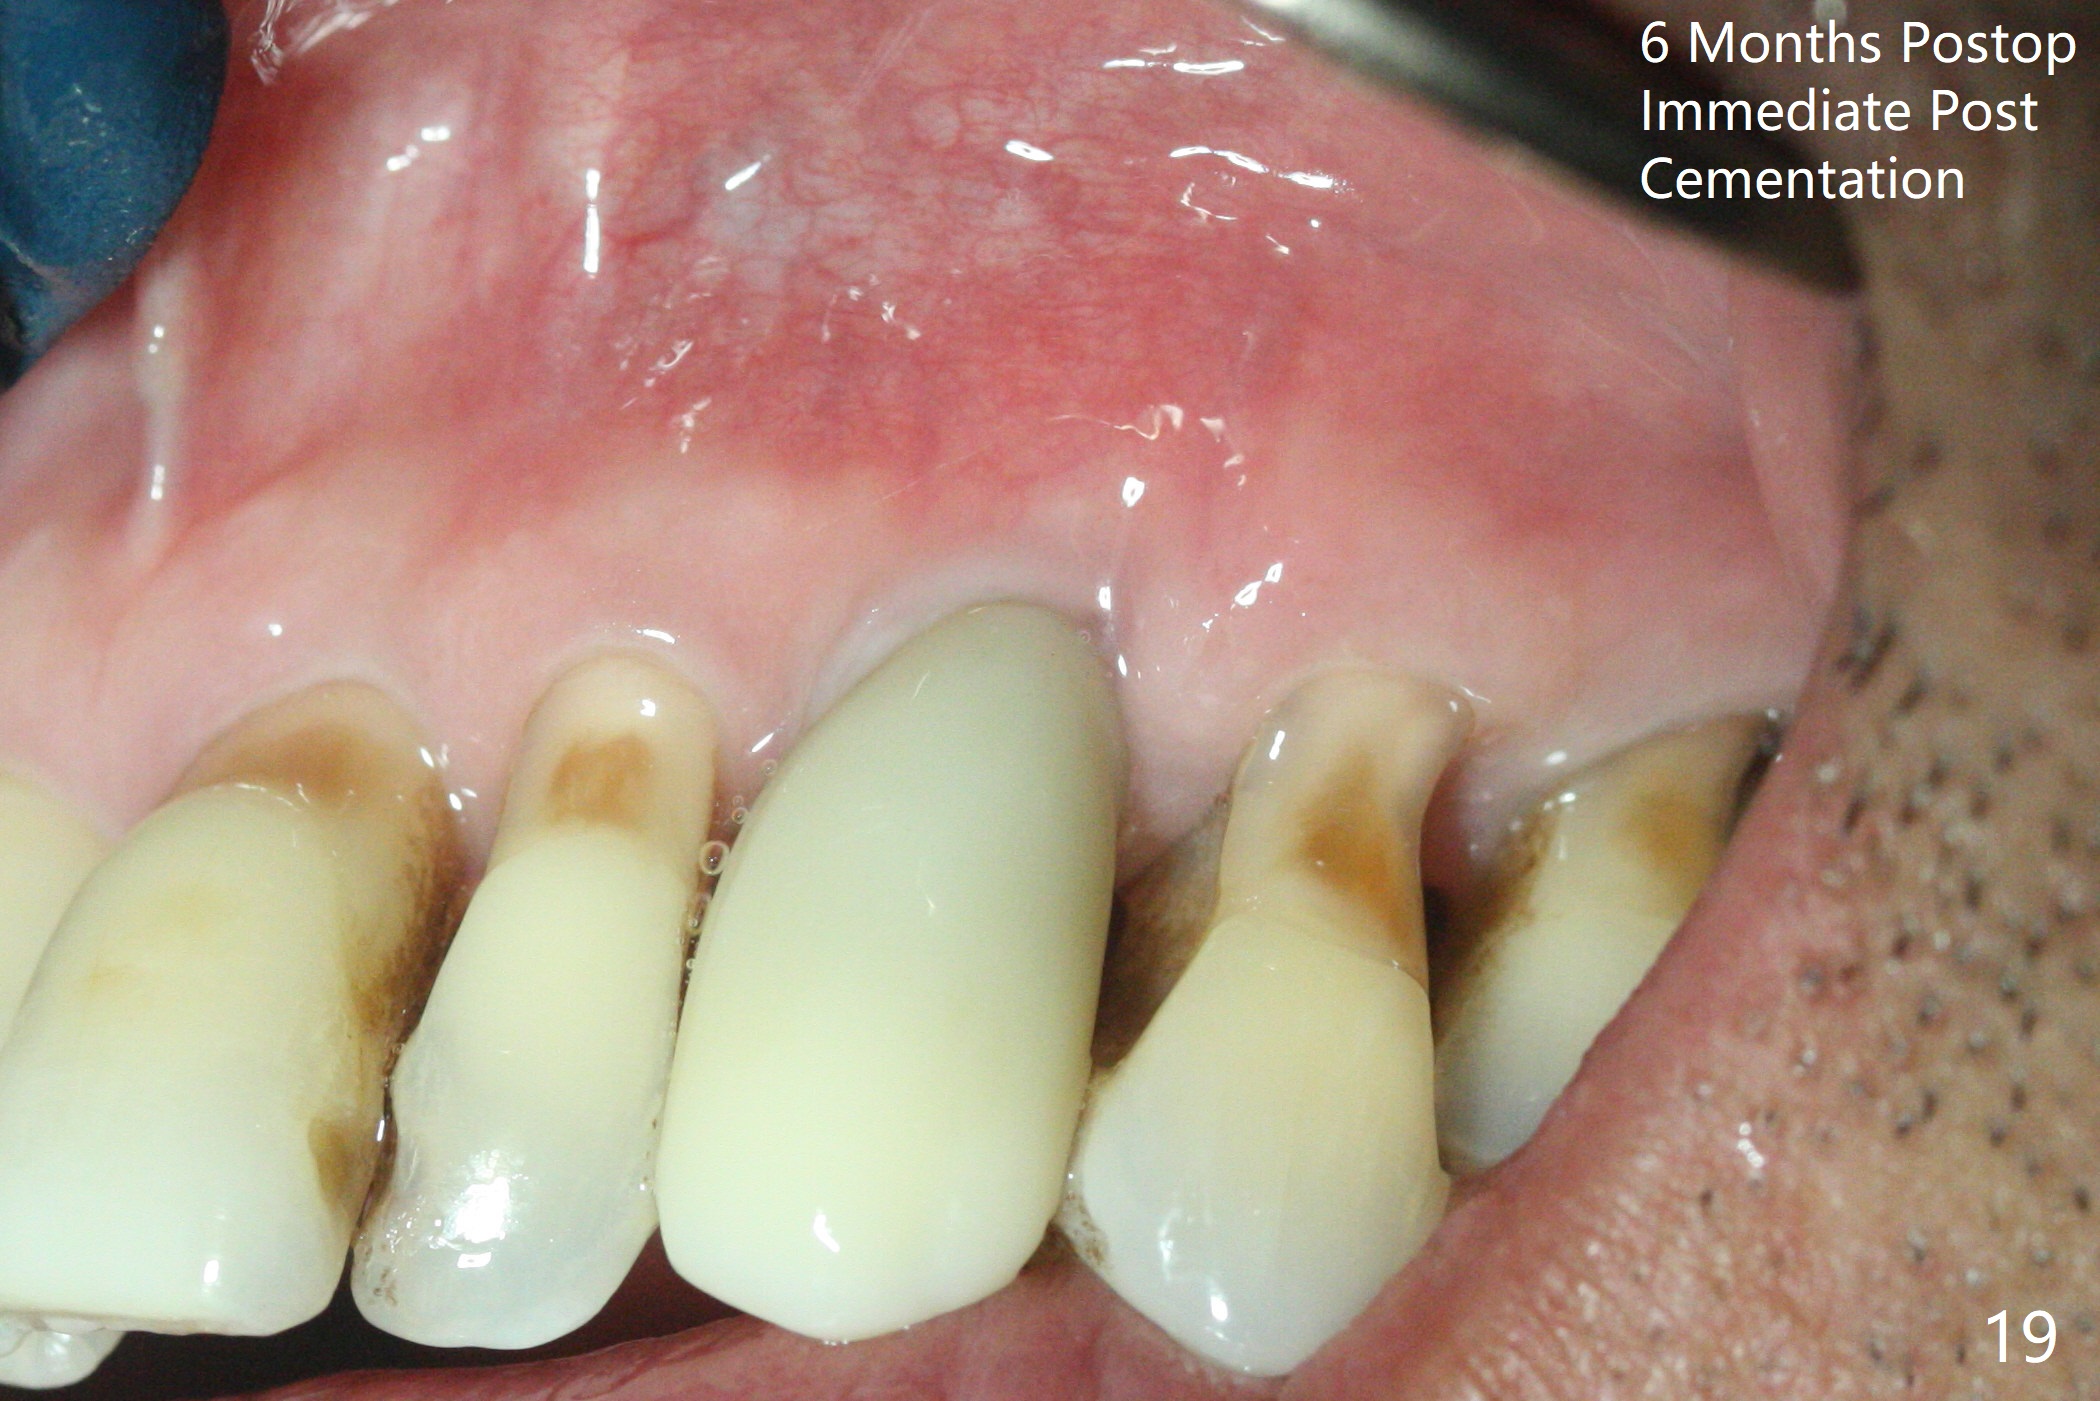

A 62-year-old man with generalized chronic periodontitis returns with chief complaint of loose tooth at #11 (Fig.1). Although a buccal fistula (Fig.1 <) is closer to #12 than to #11, percussion is more severe at #11 than 12. The buccal plate of #11 is missing, but it is possible to place a narrow immediate implant because of the wide alveolus (Fig.2). Since the gingiva is ~ 10 mm long, a mill abutment is to be used (Fig.3,5). In fact the fistula communicates with #11 extraction socket. After debridement, osteotomy is initiated (Fig.4) for a 3.8x10 mm implant ~ 35 Ncm, followed by seating a 4.5x2 mm mill abutment (Fig.5). Abundant sticky bone is placed in the remaining socket (for buccal plate reconstruction) and against the root surface of the neighboring teeth (Fig. 6 * (#10,12)). Finally 2 pieces of PRF membranes are utilized to facilitate repair of the buccal soft tissue defect (Fig.7 *). The root prominence of the canine seems to be maintained by the bone graft (Fig.8 C). Acrylic dressing holding the PRF membranes in place remains in situ with the healthy gingiva buccal (Fig.9) and palatal (Fig.10) 11 days postop. Note the acrylic locking into the undercuts of the neighboring teeth (*). 经过一段摸索发现离心每分钟1500转5分钟后,抽取上清液,接着再离心10分钟剩余上清液就形成血小板块,压制后便是血小板膜,后者似乎有助于软组织愈合,而上清液用来制备骨块,帮助硬组织生长。利用这个原则讨论以下病例治疗。The gingival margin gains ~ 5 mm 6 weeks postop when the acrylic dressing is removed (Fig.11,12 (<: previous one), as compared to Fig.7,8). 治疗结束时尖牙牙龈缘高于第一双尖牙(图七,八),六个星期后,尖牙牙龈缘却低于双尖牙(图十一,十二(箭头:原始牙龈缘))。术后2.5,4.5月基台周围牙龈似乎能与钛合金附着,防止细菌进入深部植体(图十三,十四)。临时牙冠脱落多次,可能与mill abutment太光滑有关,所以颊侧,舌侧磨成平面(图十四)。取模时好像不必取出基台清洗(仿佛没有炎症),原位用树脂延长基台。术后5个月CT显示颊侧骨板再生(图十六-十八)。取模时并没有用树脂加长基台;粘固时,牙冠颜色理想,但是照片中并不是如此(图十九,二十),颊侧骨板没有塌陷。术后11个月基台颊侧骨板没有萎缩(图二十一:B);3d图像:骨壁完全形成(图十六对比:部分形成)。密度也增高(图二十二:B),与术后五个月比较(图十七)。术后十一个月,粘固后五个月角化龈存在(图二十三),牙冠颈部有金属颜色透出,是因为二段式基台太粗了(最细4.5毫米),可以请实验室在牙冠内部涂opaque material而减轻。